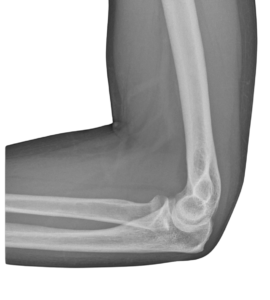

The Elbow

Unlike the shoulder, most surgeries around the elbow are done via an open approach whether its soft tissue repairs or joint replacements.

Conservative measures are always the first line of treatment where possible and surgery is a last resort option – more often than not.